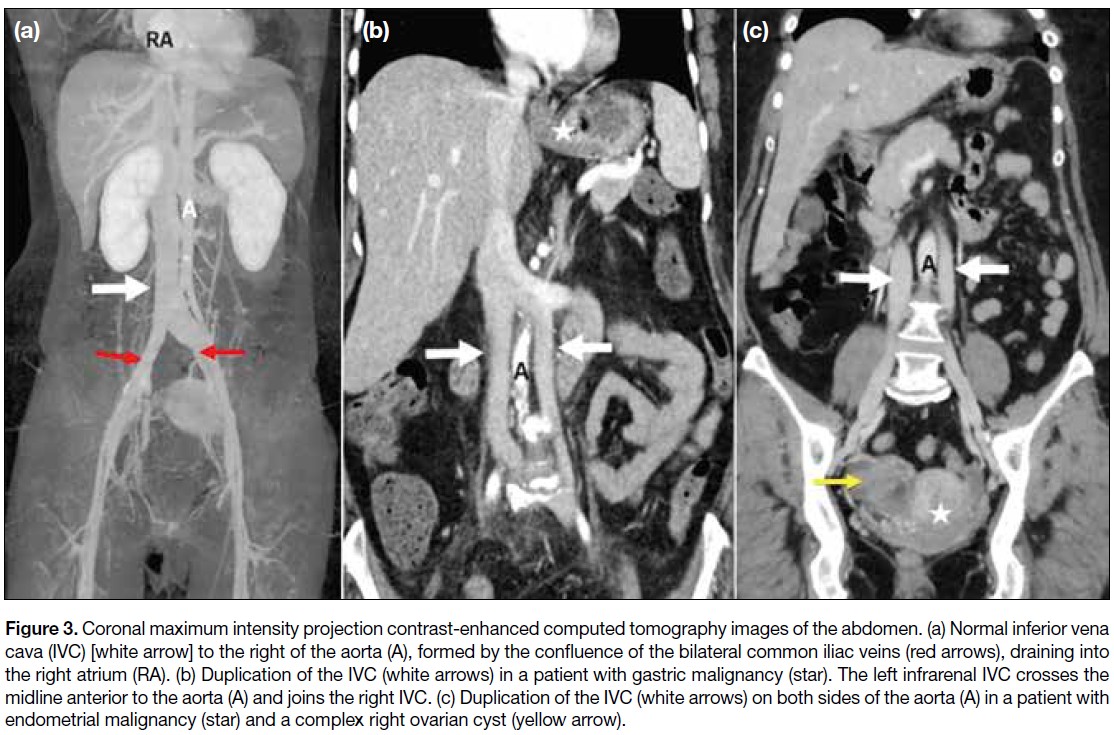

Figure 3. Coronal maximum intensity projection contrast-enhanced computed tomography images of the abdomen. (a) Normal inferior vena

cava (IVC) [white arrow] to the right of the aorta (A), formed by the confluence of the bilateral common iliac veins (red arrows), draining into

the right atrium (RA). (b) Duplication of the IVC (white arrows) in a patient with gastric malignancy (star). The left infrarenal IVC crosses the

midline anterior to the aorta (A) and joins the right IVC. (c) Duplication of the IVC (white arrows) on both sides of the aorta (A) in a patient with

endometrial malignancy (star) and a complex right ovarian cyst (yellow arrow).